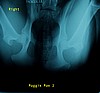

MaggieMae

Maggie radiography appointment was February 15, 2007.

PennHip recieved these x-rays February 20, 2007 with the report date February 22, 2007.

DI scores = (Left) 0.36 / (Right) 0.36

These photos are the actual x-rays PennHip used for their evaluation/measurements. Click on each photo for a larger view.